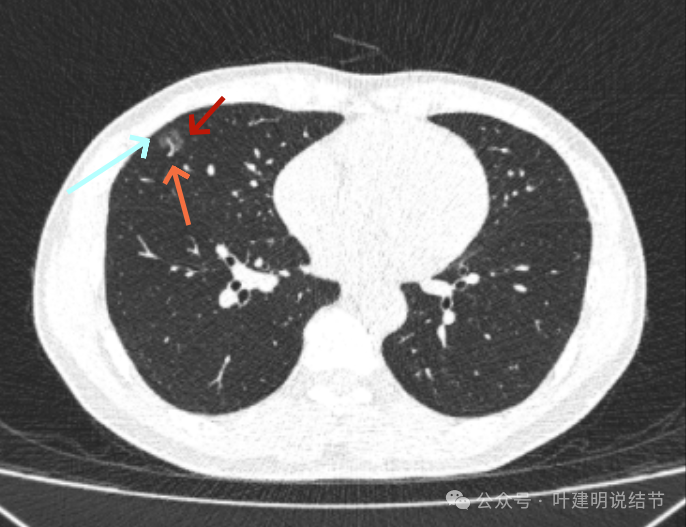

2023年10月时病灶又有进展,表面有细毛刺、灶内血管明显异常增粗,中间仍有小的空泡征,整体轮廓与边界清,大小也有所增大。磨玻璃部分的密度也较之前有所增加。

病灶出现,磨玻璃密度,轮廓较清,有微血管进入。

分叶征明显,灶内似有细支气管扩张,表面不平。

胸膜间隙征存在;血管进入与异常增粗,边缘细毛刺,整体轮廓与边界清。

中间仍有空腔征,表面细毛刺,整体轮廓清。

囊壁密度不均,有少许偏实性成分,边缘细毛刺,有小血管进入。

毛刺征明显且典型,血管进入并增粗,邻近胸膜似略有牵拉影响。

边缘部分也密度欠均匀,相应胸膜稍有牵拉影响。

表面不平,轮廓清,有分叶,有胸膜牵拉。

边缘也是磨玻璃成分,边界与轮廓清楚。